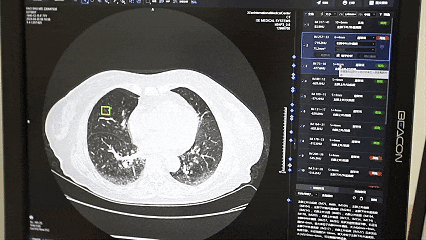

「智慧赋能」拉开该院系列微改革的帷幕。像上述王先生所体验的「诊间支付」,已在全院近百个诊室推开。这只是「便民就医少跑腿」多项举措中的一项。线上问诊、移动支付、智慧病房、数字化手术室、远程监测、智能随访以及 AI 诊断、秒等取药、智能导医、气动物流、机器人等,为医院插上智慧的翅膀,让智慧化遍布就医每一个环节,也让患者感受到数字技术带来的变化及智慧医院带来的快捷。

2025 年 2 月 20 日,在西北首家本地化成功部署 DeepSeek-R1 大模型之后,该院又推出了「国医小助」智能辅助诊疗系统,在患者服务、辅助医疗诊断和医院管理三方面展现出强大的能力。院内智能导航精准引路、床旁移动结算、线上病案复印等服务陆续上线,让「信息多跑路,群众少跑腿」变为现实。